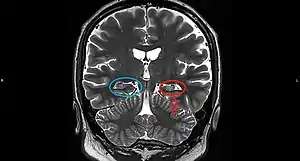

Hippocampal sclerosis (HS) or mesial temporal sclerosis (MTS) is a neuropathological condition with severe neuronal cell loss and gliosis in the hippocampus.[1] Neuroimaging tests such as magnetic resonance imaging (MRI) and positron emission tomography (PET) may identify individuals with hippocampal sclerosis.[2] Hippocampal sclerosis occurs in 3 distinct settings: mesial temporal lobe epilepsy, adult neurodegenerative disease and acute brain injury.[2][3]: 1503

On a MRI T2-weighted or T2–fluid‐attenuated inversion recovery (FLAIR) scan, hippocampal sclerosis appears as an increased signal, smaller sized (atrophic) hippocampus with a less well-defined internal structure.[2] Increased signal means that hippocampal sclerosis will appear brighter on the MRI image. Less well-defined internal structure means the expected sharp boundaries between hippocampal gray and white matter structures are absent.[2] The total volume of the hippocampus is also reduced.[2] The reduced volume arises from neuronal cell loss, and increased signal arises from gliosis.[2]